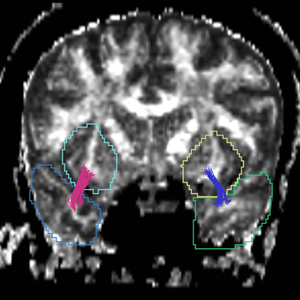

Region

caseD00917

caseD00920

caseD00924

caseD00928

caseD00935

caseD00936

caseD00938

caseD00939

caseD00940

Uncinate Fasciculus

Internal Capsule

Fornix

Cingulum

Arcuate Fasciculus